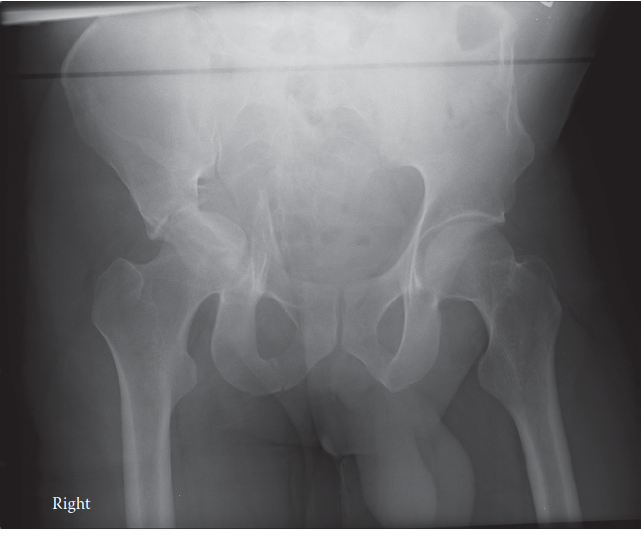

Advanced osteoarthritis bilaterally. Osteonecrosis and complete obliteration of the joint space on both sides…